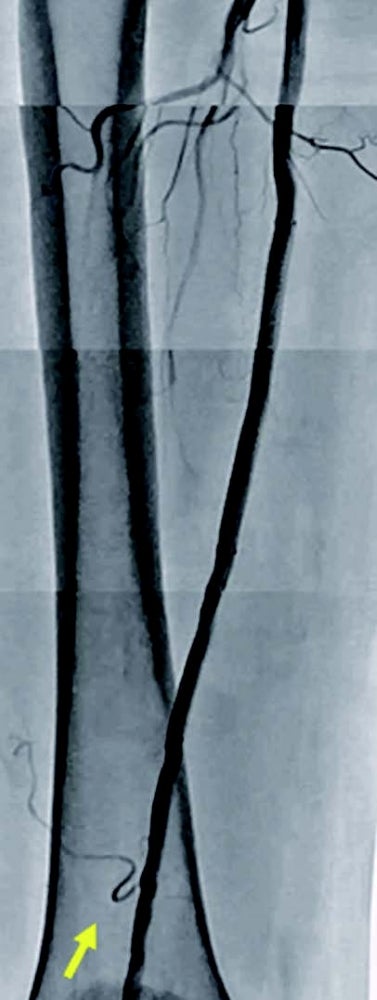

右浅大腿動脈閉塞(図3): 左鼠径部を穿刺(6 Fr シース)しcrossover後、順行性に0.014 inchマイクロカテーテルを使用して0.014 inch ガイドワイヤー(先端荷重1 g →3 g →40 g)を進めたが貫通できず、足背動脈を穿刺し逆行性に0.014 inch ガイドワイヤーを進め、貫通に成功。IVUS catheterで一部 subintimal trackingしていることを確認。5.0 mm 径バルーン(non-compliant balloon)で拡張後解離が生じ、末梢にバイアバーン® ステントグラフト5.0 × 150 mm、中枢に6.0 × 250 mm の2本を留置。病変の末梢には発達した2本の側副血行路を伴い、側副血行路の間に軽度狭窄病変を認めたため、中枢側の側副血行路をjailさせ、健常部にバイアバーン® ステントグラフトを留置。5.0 mm 径と6.0 mm 径バルーン(non-compliant balloon)で後拡張して終了。(図4)